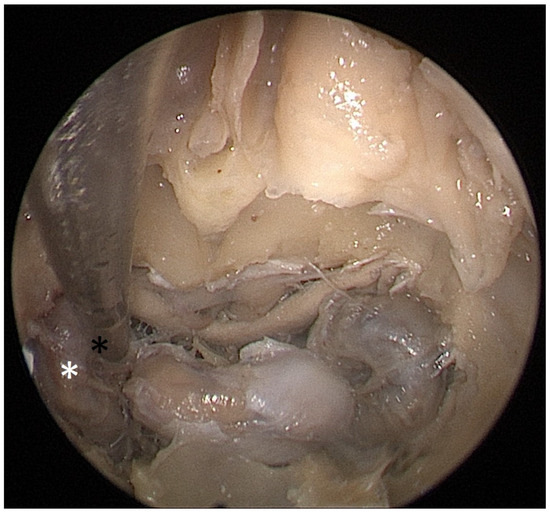

Cadaver pituitary surgery: On each of the two cadaveric heads, we used the paraseptal binostril approach for the sphenoid sinus. A 30° Storz endoscope (Karl-Storz, Austria, Vienna) was used. The head was mounted in a Mayfield cranial stabilization device. The surgery started with a lateralization of the inferior and medial turbinates. The anterior sphenoid wall and ostium to sphenoid sinus were identified. Using the straight suction with a marked scale, 1 cm and 2 cm distances from the anterior sphenoid wall were measured and marked with a scalpel on the posterior part of the septum. Using a scalpel, Kerrison punch, and backbiter punch, a posterior septal resection 1 cm from the anterior wall of the sphenoid was performed. We continued with the wide opening of the sphenoid cavity and resection of the intersphenoidal septum and the full exposure of the posterior wall, both ICAs, and optocarotic recesses (OCR). The posterior wall of the sphenoid sinus and dura were resected to better identify anatomic landmarks, with both ICAs, pituitary gland, chiasma, and optic nerves visible at the end of a resection (Figure 4). The straight suction was inserted into the sphenoid sinus so that the instrument’s tip was in the most lateral position in the sphenoid sinus without infracturing the rest of the nasal septum. A picture was taken in this position to evaluate the most lateral part of the sphenoid sinus that could be reached with a straight instrument with a 1 cm septal resection without infracturing the nasal septum (Figure 5). Enlargement of the septal resection to 2 cm from the anterior sphenoid wall was performed with a backbiter punch and scalpel. The straight suction was inserted into the sphenoid sinus so that the instrument’s tip was in the most lateral position in the sphenoid sinus without infracturing the rest of the nasal septum. A picture was taken in this position to evaluate the most lateral part of the sphenoid sinus that could be reached with a straight instrument, with a 2 cm septal resection, without infracturing the nasal septum (Figure 6).

Each head was operated on twice. First, a binostril approach and a 1 cm posterior septal resection were performed. This allowed us, in both cadavers, to comfortably reach the medial part of the carotids bilaterally with straight suction. This resection size would be sufficient for a safe tumor extraction in non-extended tumors. Then, a 2 cm extension of the septal resection was performed. A more extensive resection allowed us to reach the lateral margin of the ICA bilaterally. It also gave us better maneuverability and an overview of the operated area.

Figure 6. Opened sphenoidal sinus, endoscopic view, straight suction (black asterisk) reaching lateral margin of ICA (white asterisk) with 2 cm septal resection.